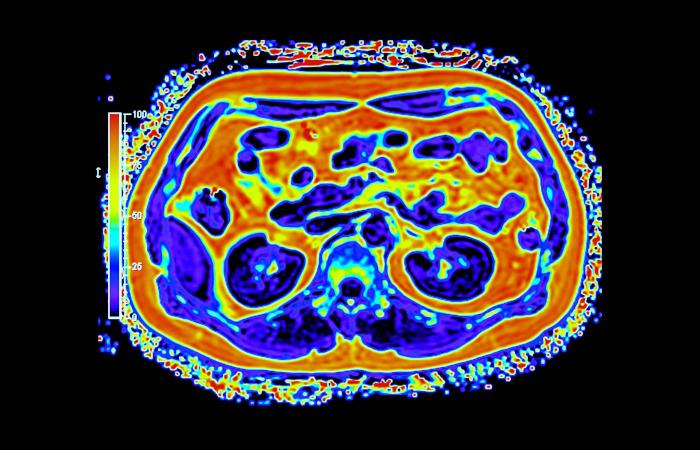

وعلى خلاف التصوير التقليدي، يجمع التصوير الجزيئي بين التفاصيل التشريحية والبيانات الوظيفية الآنية، ما يتيح للأطباء رؤية كيفية عمل الأنسجة لا مجرد شكلها. وفي مجالَي الأورام والأمراض العصبية، قد يُحدث هذا الفرق تحولاً في توقيت الاكتشاف أو في تعديل خطط العلاج أو في تجنّب إجراءات غير ضرورية. غير أن توسيع هذه القدرات عبر بلد واسع ومتنوّع جغرافياً يطرح تحديات تتجاوز كثيراً مجرد اقتناء الأجهزة.

أحرزت السعودية تقدماً تدريجياً في نشر أنظمة التصوير المتقدم، بما في ذلك «PET - CT» و«PET - MRI» داخل مراكز طبية كبرى. وبحسب الدكتور سامح الشيخ المدير العام لشركة التصوير الجزيئي والقطاع الطبي بوادي جدة، أثبتت هذه التقنيات قيمتها السريرية عبر الكشف عن انتشار سرطاني أو اضطرابات لم تُظهرها وسائل التصوير التقليدية، ما أتاح تعديل العلاج فوراً في عدد من الحالات.